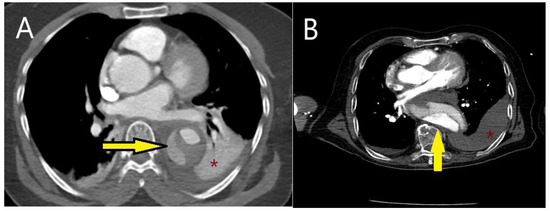

5.2.3. Computed Tomography

5.2.4. Magnetic Resonance Imaging (MRI)